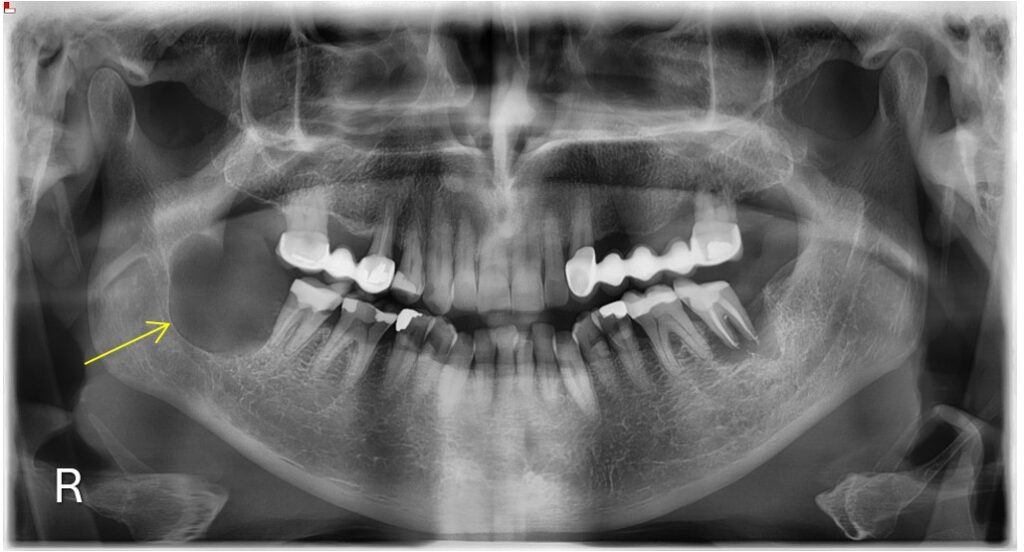

Άνδρας ασθενής 77 ετών εμφάνισε προ 4 ετών ενδοστοματικό ογκίδιο για την ακτινολογική διερεύνηση του οποίου συστήθηκε η πραγματοποίηση πανοραμικής ακτινογραφίας. Στην πανοραμική ακτινογραφία παρατηρήθηκε η παρουσία ευμεγέθους ακτινοδιαυγαστικής αλλοίωσης η οποία απεικονίζεται στην περιοχή της αναφερόμενης ενδοστοματικής βλάβης.

Πανοραμική Ακτινογραφία 12/2020